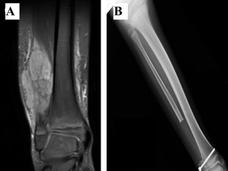

Ifosfamide May Be Treatment of Choice for Some People with Ewing Sarcoma, Trial Shows

New findings from the first large, randomized clinical trial to compare chemotherapy regimens for relapsed or treatment-resistant Ewing sarcoma could help doctors and patients select treatments.